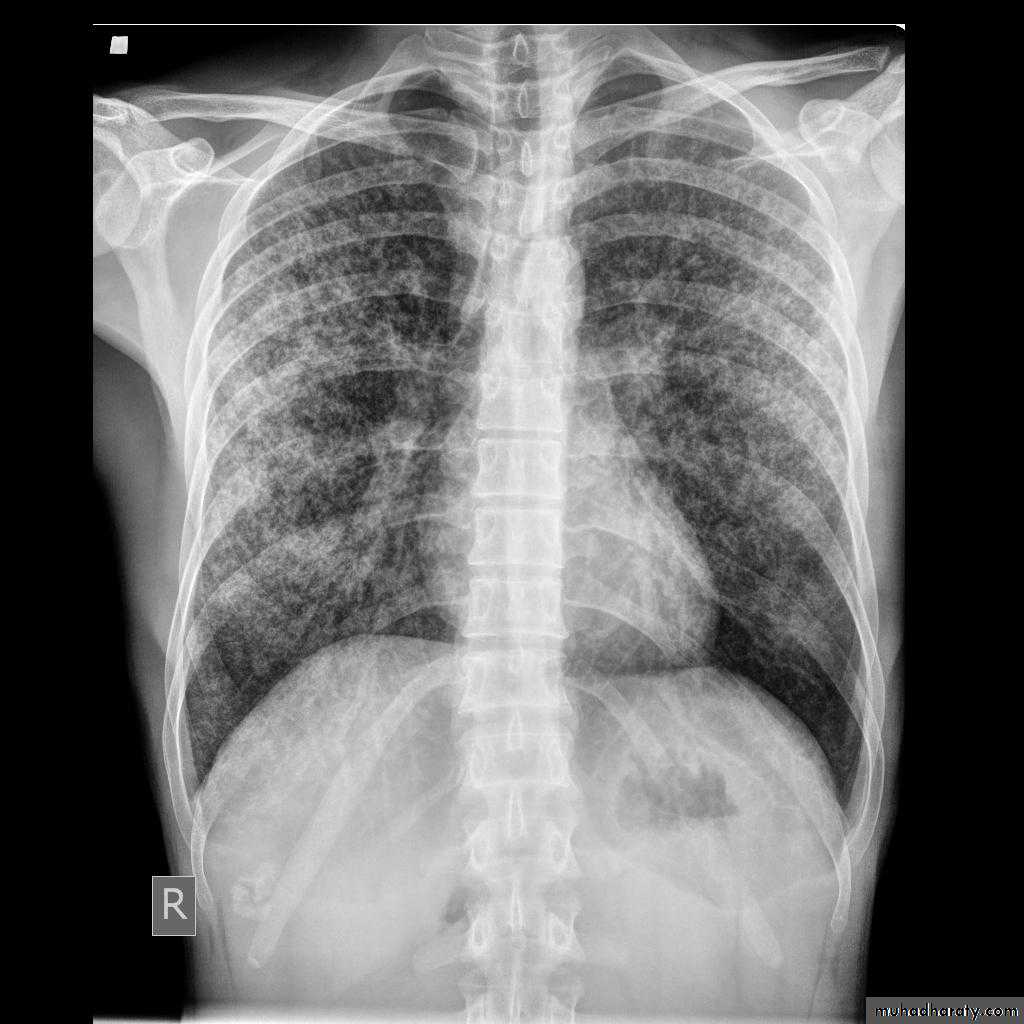

Miliary TB

65.Miliary TB

66. miliary TB